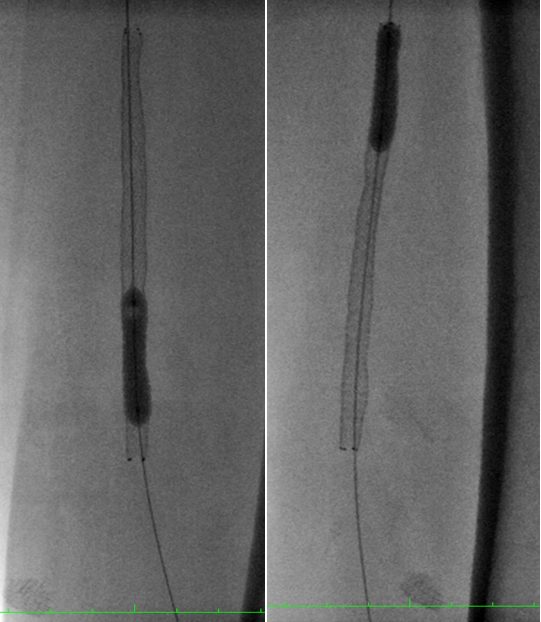

使用Sterling球囊预扩张后植入Eluvia DES的病例。IVUS评估显示,支架植入后管腔获得显著,但在支架局部不规整处最小径仅为3.7mm,提示局部扩张可能不充分。

图:Sterling球囊预扩张(3-150mm、5-100mm)